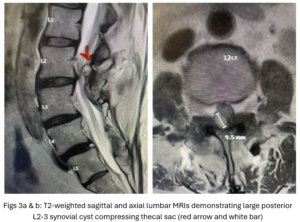

Figs 1a,b: T2-weighted sagittal and axial MRI demonstrating (red arrow) a large right L4-5 foraminal synovial cyst. Note the grade 1 spondylolisthesis (blue arrow)

This 54-year-old female with a long history of low back pain presents with three weeks of a progressive right footdrop with associated numbness and tingling of the right leg. In addition, she had right lateral hip pain down to the dorsum of her foot. She first noticed her right foot slapping the floor when she walked. She had no prior trauma or unusual activity before this began. Her chiropractor, who had treated her back pain for a long time, first noticed the foot drop and referred her for further evaluation. She presented with ⅖ strength in her right dorsiflexor. MRI revealed a large right L4-5 foraminal synovial cyst with some mass-effect on the thecal sac. (Fig. 1) She also had an associated grade 1 spondylolisthesis. Because the cyst was more foraminally-oriented, it had the majority of its effect on the right L4 nerve root. It was felt the patient required surgery to attempt to reverse her weakness. We performed a decompressive laminectomy at L4, removing the inferior facet process on the right in order to gain lateral and foraminal access to the right L4 nerve root. In the lateral recess there was a heap of inflammatory tissue which we entered, revealing the cyst. The medial wall was stuck to the dura. We internally decompressed the cyst which was mainly gelatinous material with some fluid. We dissected and removed as much of the cyst we could safely remove but left the medial wall for fear of removing it would cause a CSF leak, upon removing the bulk of the cyst we encountered anteriorly the descending and exiting right L4 nerve root which was purplish in color and clearly inflamed. We performed a generous foraminotomy of the right L4 as well as the right L5 nerve root. We also performed an instrumented fusion at L4-5 (Fig. 2).